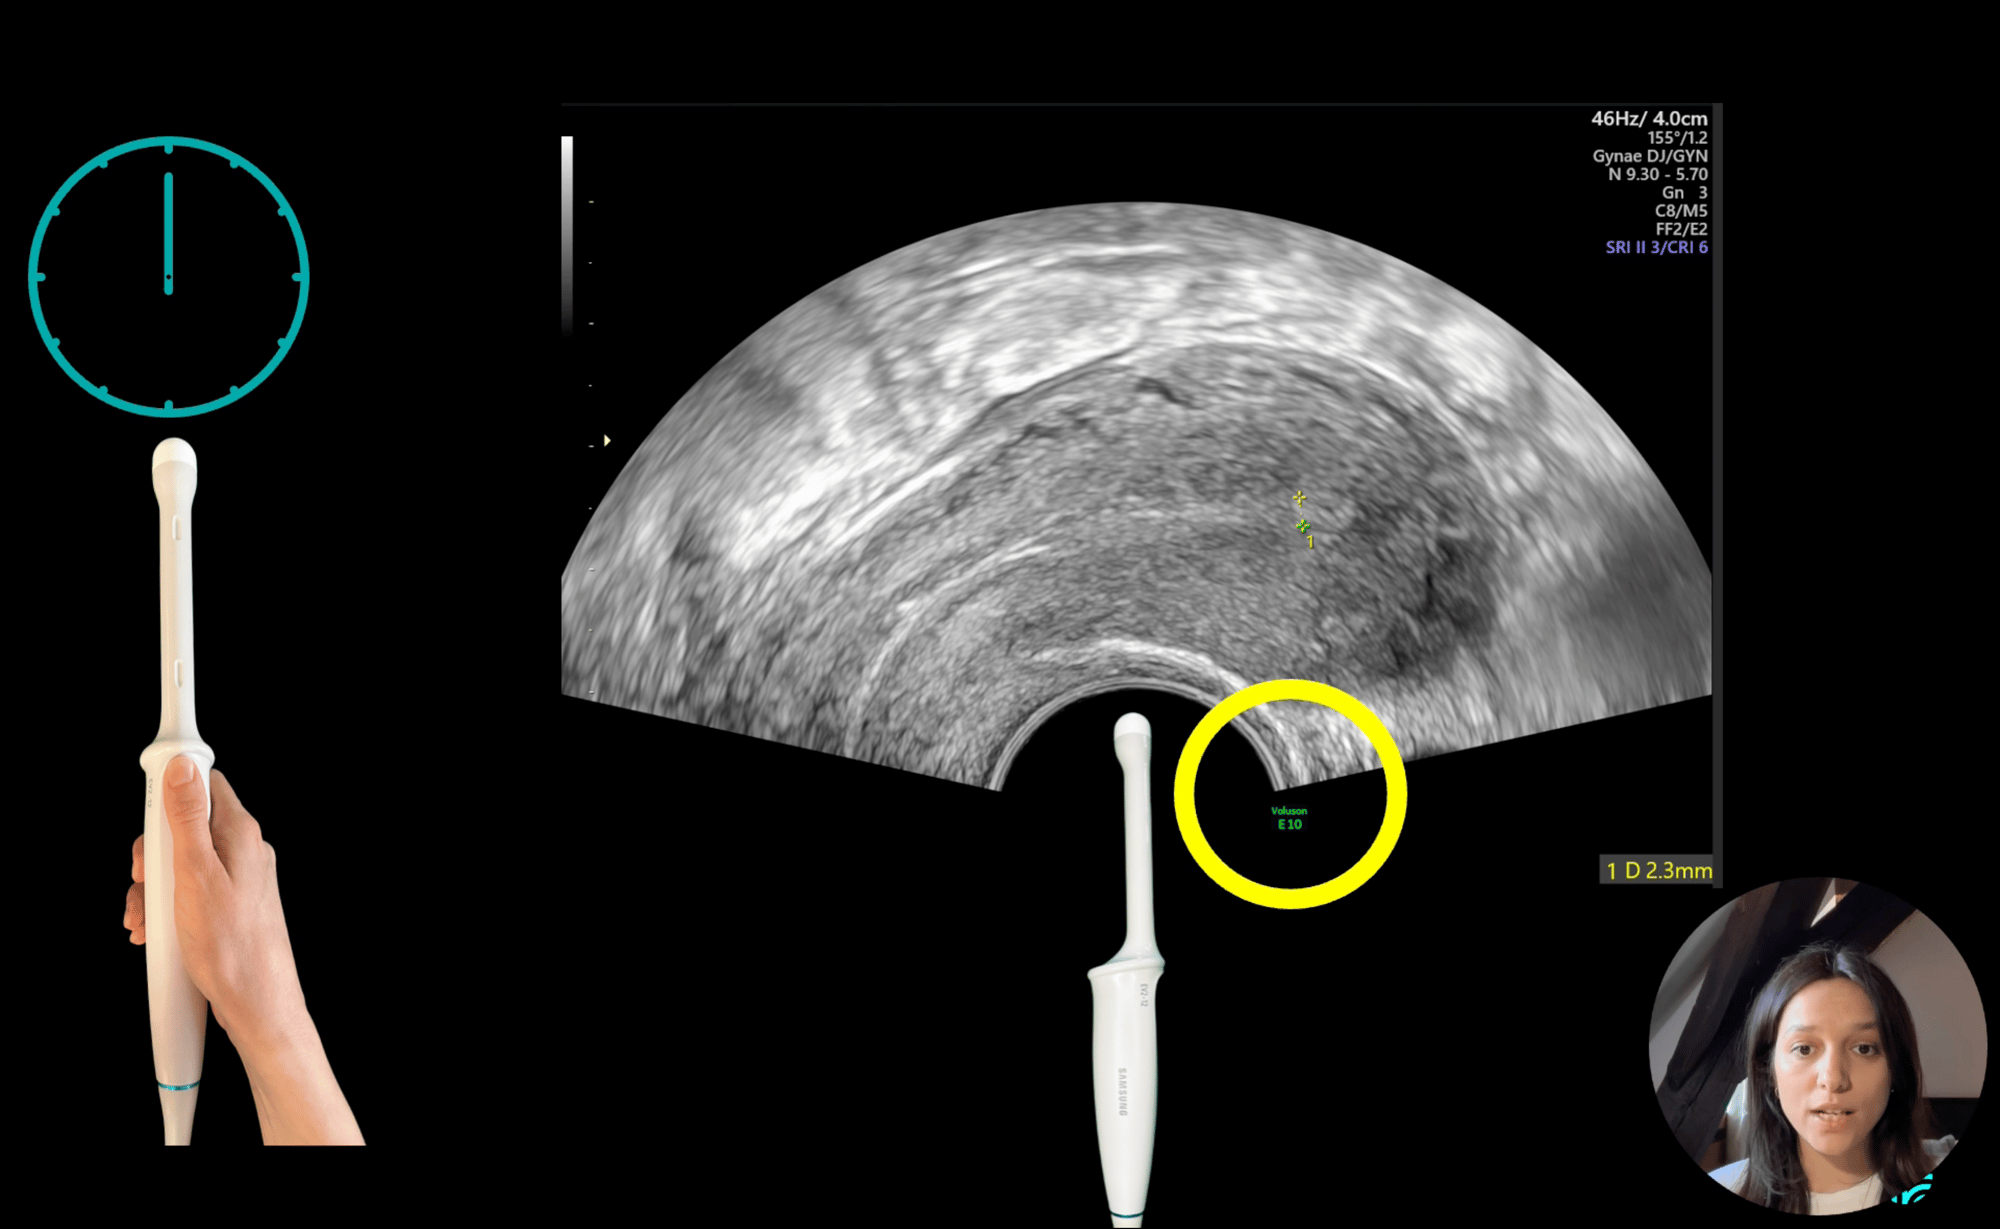

Comprehensive training programmes for ovarian masses, uterine assessment, early pregnancy care, and endometriosis.

Gynaia’s Training & Certification Programmes combine continuous education with structured learning, and expert insight with clinical practice.

Developed from over two decades of IOTA consortium research and diagnostic experience , our programmes set the reference standard for gynecological ultrasound training and assessment.

The curriculum reflects contributions from leading experts and is illustrated by real-life clincal cases throughout.